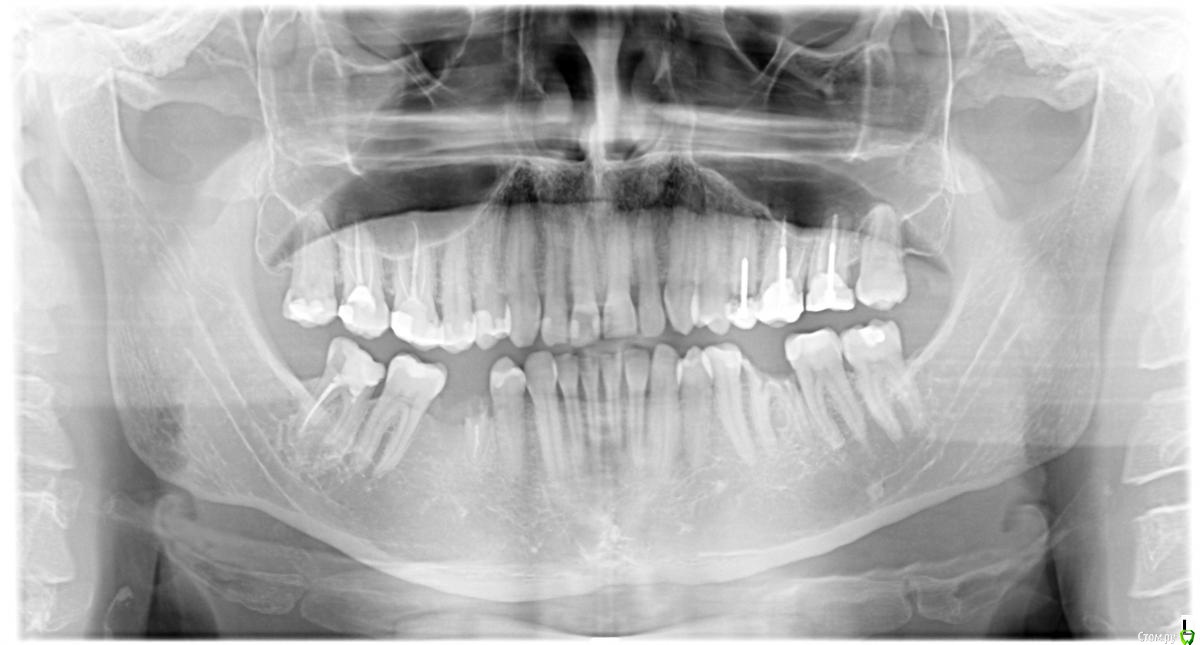

Добрый день! Собрался заняться зубами. Обошел несколько клиник т.к. мнения у врачей разделились, хотел бы проконсультироваться здесь.

1. Зубы 17, 18 покрыть коронками (нужно ли перелечивать каналы?).

Один врач на КТ увидел затемнения сбоку зубов у корней предложил, удалить.

2. 25 зуб сказали на удаление, один врач предложил попробовать пролечить. Имеет ли смысл попробовать перелечить.

С таким корнем хожу уже больше 5 лет точно.

3. 26 и 27 коронки, на 27 скол почти до десны. несколько врачей предложили так же их удалить.

4. 36 удаление, имплантация.

5. 45 удаление, предлагают одномоментную имплантацию или отсроченную. 46 зуб был удален давно кость тонкая,

возможен ли вариант вместо 45 и 46 поставить один имплант после костной пластики или нужно 2 импланта?.

6. 48 можно восстановить коронкой с пролечиванием каналов? Или тоже под имплантацию. Имеет ли смысл в принципе перелечивать и ставить коронку на восьмерку?

Как я понимаю сначала лучше поставить коронки. А затем заняться имплантами. На каком этапе лучше заняться удалением.